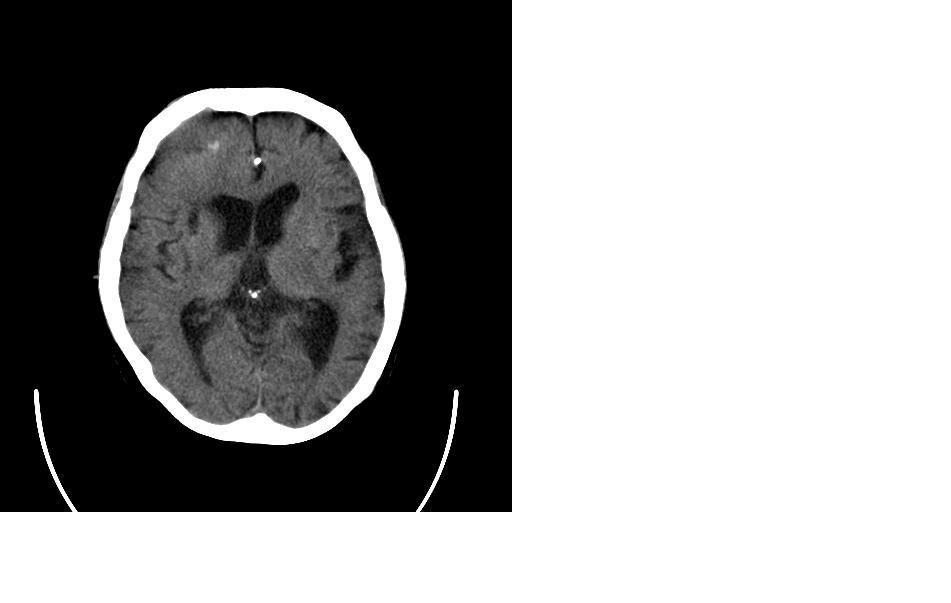

女,77岁,渐进性突眼2年,无其他明显症状

右额窦粘液囊肿,向前累及筛窦并进入眼眶使眼球前突;向下进入颅内右额叶脑质及侧脑室受压

支持:病变的起源我乐意定在右额窦。右额窦粘液囊肿或粘液腺癌累及筛窦、眼眶使眼球前突;向下进入颅内右额叶脑质及侧脑室受压变形。

定位:来源右额窦。定性:良性占位—额窦黏液囊肿。理由1、病灶中心位于右额窦区,侵及筛窦并向下向前压迫眼球2、骨质呈膨胀性改变,骨质弓形变薄但骨壳完整,如为恶性骨质应为侵蚀性破坏3、黏液囊肿好发于筛窦、额窦。